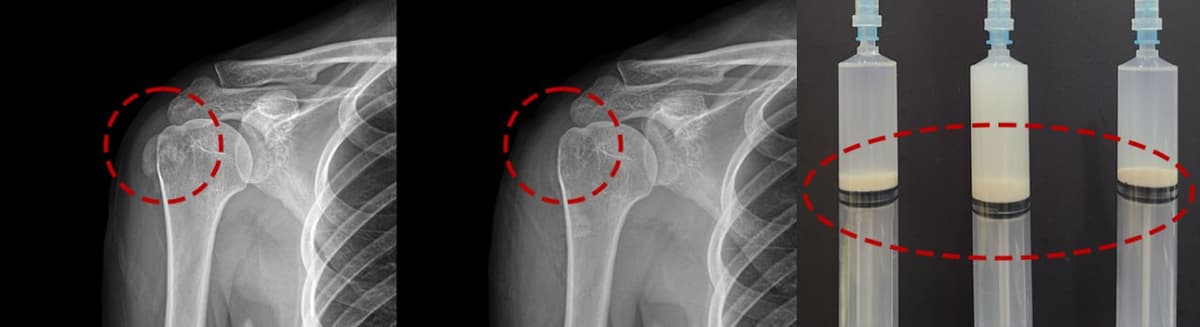

Before & After X-ray

Even hardened calcium completely removed after a single session. Real patient X-rays.

White calcium mass clearly visible in the shoulder tendon on X-ray.

Calcium completely removed after a single crushing aspiration procedure.